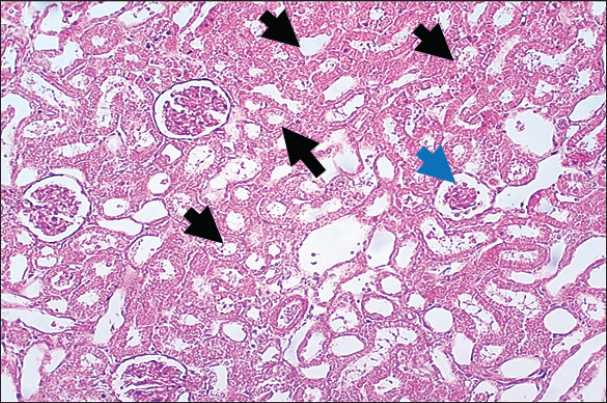

In the control group, histological analysis of kidney sections revealed intact glomeruli and renal tubules (Fig. 1). Conversely, Figure 2 presents a kidney section from the green tea group, which exhibited normal renal tubular epithelial cells, a well-preserved tubular lumen, and an overall normal tubular texture, although some glomeruli showed mild atrophy. The renal section of gentamicin showed atrophy of the glomerular tuft, expansion of the globular space, and significant hyperemia lesions in some glomeruli associated with substantial damage to the superficial cell layer (epithelial cells) in the proximal renal tubules, resulting in a reduction of the tubular lumen space (Fig. 3). In contrast, kidney sections from the gentamicin group that received green tea treatment revealed a marked reveal of both glomeruli and renal tubular epithelium, which appeared normal (Fig. 4 and Fig. 5).

Fig. 2. Rat kidney treated with green tea extract the section shows normal renal tubular epithelial cells with normal tubular lumen (Black arrows), normal tubular texture, and mild atrophy can be seen in some glomeruli (Blue arrows). H and E (10X).